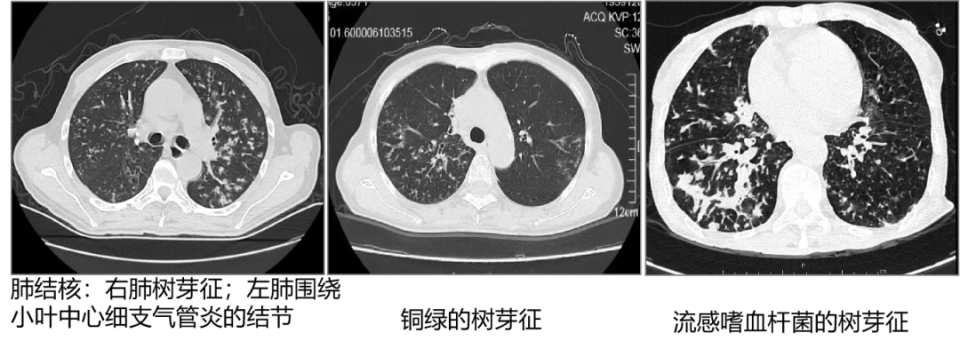

3. 树芽征:是胸部薄层 CT 扫描发现的一个征象,是小叶中央细支气管被黏液、脓液或液体等填充并扩张,形成类似树芽般的阴影。树芽征提示支气管肺炎,是支气管肺炎最初的纵切形态。

4. 围绕小叶中心细支气管的结节:是支气管肺炎最初的横切形态,并且支气管外的渗出稍增多。

2. 支气管肺炎(小叶性肺炎):金黄色葡萄球菌肺炎、铜绿假单胞菌肺炎、流感嗜血杆菌肺炎、大肠埃希菌肺炎、阴沟杆菌肺炎、肺结核及非结核分枝杆菌肺炎、支原体肺炎、肺念珠菌病、丝状真菌肺病等。

2.  肺泡性肺炎的最初形态是腺泡结节;支气管肺炎的最初形态是树芽征及围绕小叶中心细支气管的结节;间质是肺内与空气不接触的部分,间质性肺炎有 4 种模式:线样影、网格影、结节影、网结影。